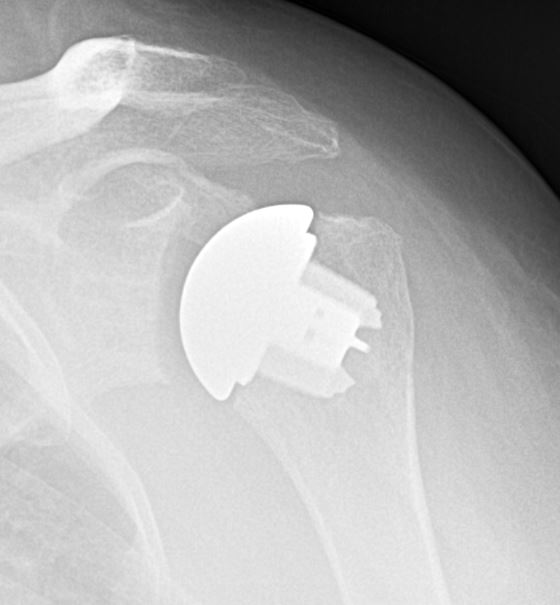

Anatomic Shoulder Replacement